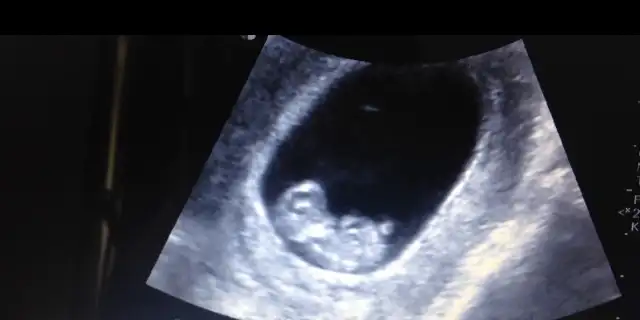

Eki Görüntüle 2130382 benim ikizlerim şimdi den sıkıştırma ya basladilar bana dua edin